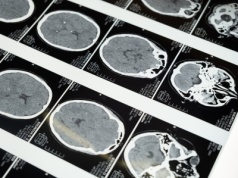

Jeden z najstarszych leków na nadciśnienie hydralazyna blokuje wzrost glejaka

Przełomowe odkrycie: popularny lek na nadciśnienie może hamować agresywne guzy mózgu. Artykuł Jeden z najstarszych leków na nadciśnienie hydralazyna blokuje wzrost glejaka pochodzi z serwisu Alert Medyczny.